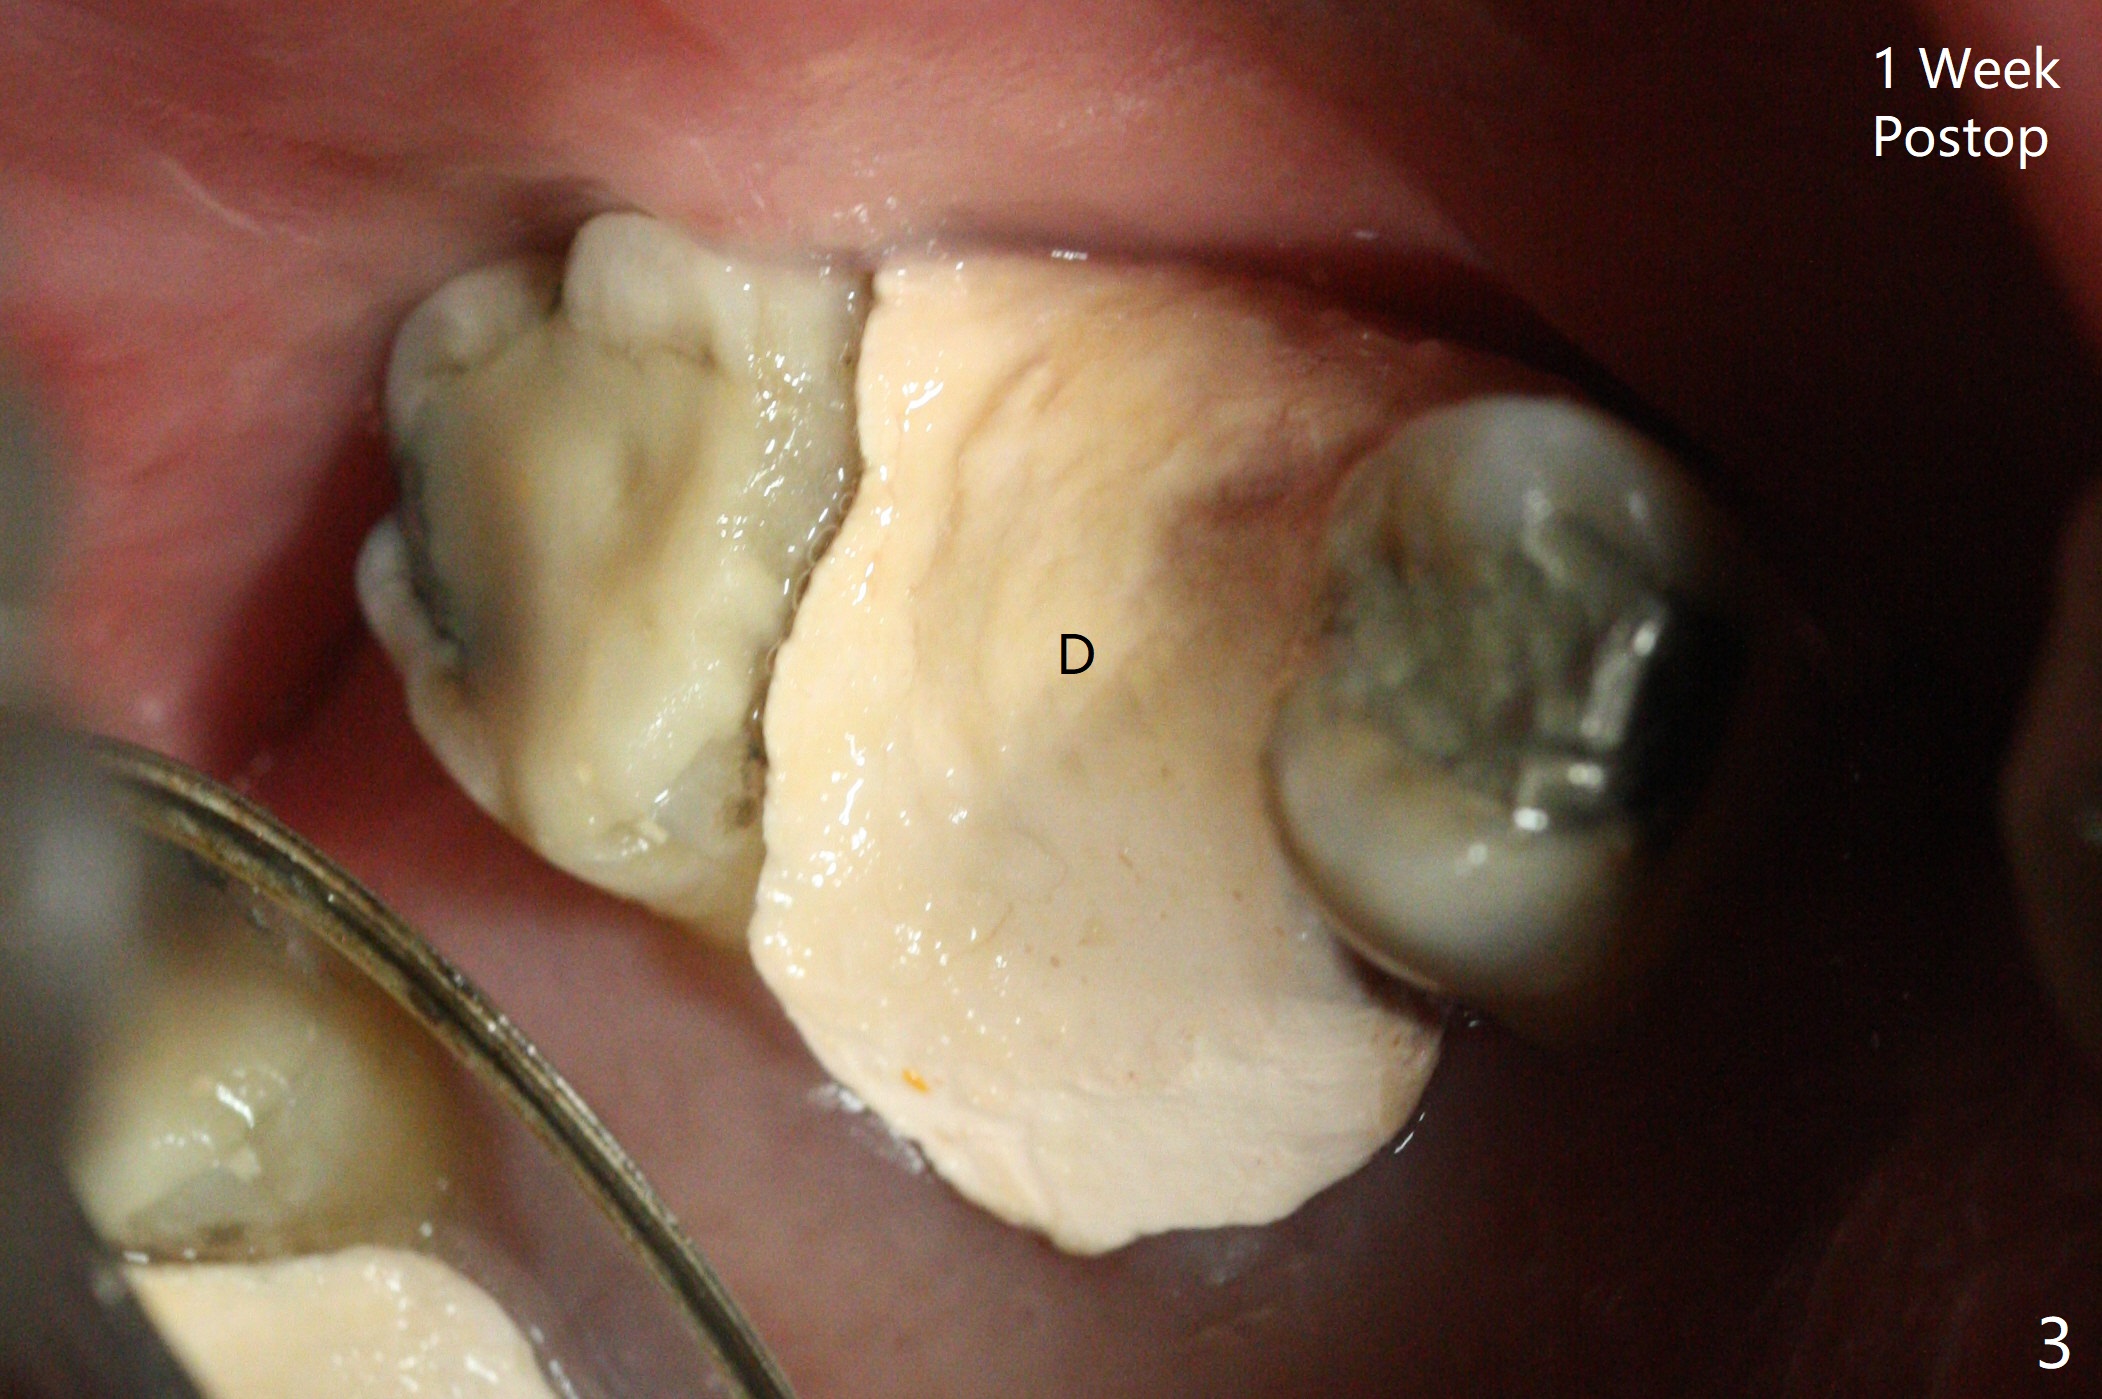

Since the tooth #3 has severe chronic periodontitis with 1 mm sinus floor (Fig.1 *), socket preservation may be not secure (B) in spite of using Cytoplast and PTFE suture. Prior to the bone graft, the sinus floor is lifted easily with Magic Sinus Lifter (IBS America) with Ossogen (mineralized cortical/cancellous (30%/70%) allograft, Fig.1,2 L). Periodontal dressing remains in place because of the neighboring teeth 1 week postop (Fig.3 D). Cytoplast remains in place after dislodgement of the periodontal dressing 2 weeks postop (Fig.4). Cytoplast dislodges 3 weeks postop (Fig.5). Socket preservation is not as secure as immediate implant in term of bone graft retention. What else can be done to prevent bone graft loss?